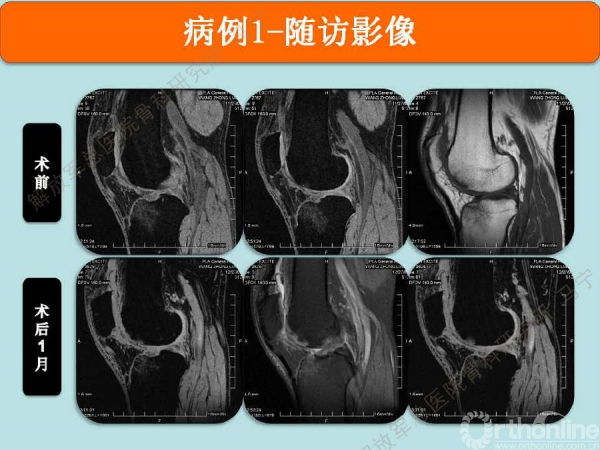

病例1

患者右膝疼痛6年,无绞锁,特别是蹲起困难,于2008年住我院,接受关节镜手术,发现股骨滑车局部软骨缺损。

术后8个月修复区的软骨厚度恢复理想,软骨下骨水肿信号不明显。术后16个月复查修复区的软骨没有太明显的变化。